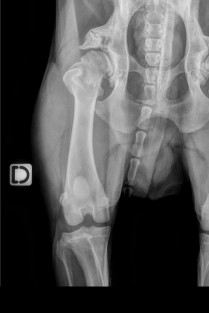

L’arthrose est la première affection articulaire rencontrée chez le chien. Cette formation a pour objectif de faire le point sur cette affection en abordant les moyens actuels d’évaluation et de suivi de l’animal arthrosique et la prise en charge multimodale du patient arthrosique.

Plusieurs présentations seront axées sur le dépistage précoce et la prise en charge des atteintes articulaires évoluant régulièrement en arthrose telles que les dysplasies du coude et de la hanche, la rupture du ligament croisé, et les atteintes vertébrales.

Actualités dans la prise en charge de la dysplasie du coude

Comment prévenir la coxarthrose ? Dépistage précoce de la dysplasie de la hanche

Diagnostiquer et traiter une rupture du LCA avant que l’arthrose ne s’installe dans le grasset